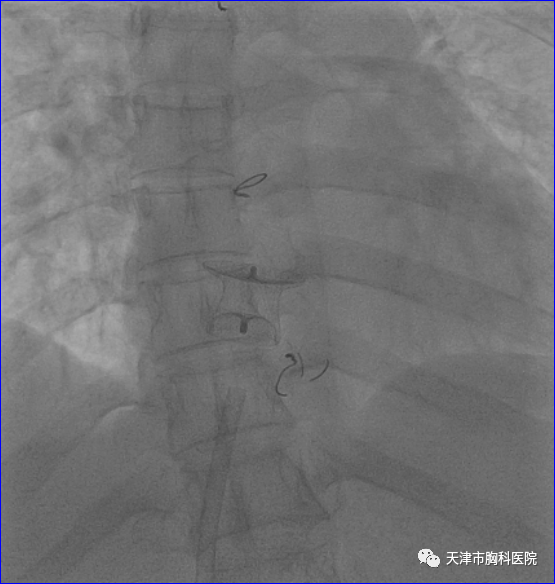

文章图片

(封堵器成功置入后影像)